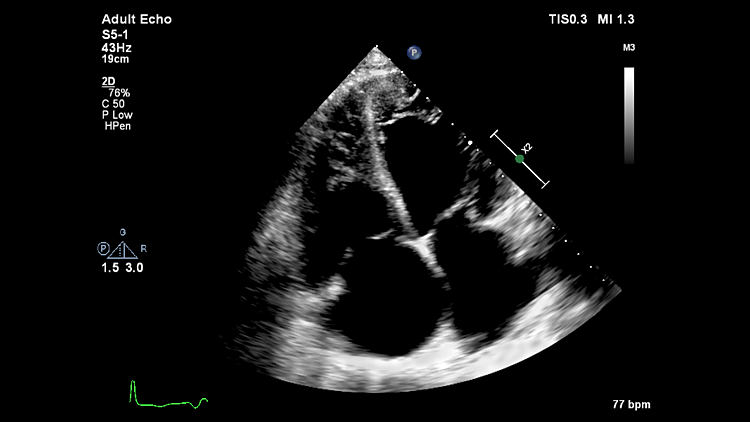

Эхокардиография, S5-1